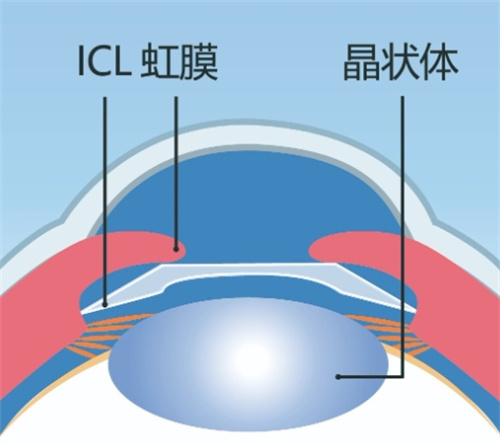

人工晶体植入术(ICL)通过在眼内植入一个特殊的人工晶体来矫正视力,这种手术避免了切削角膜的风险,且对角膜厚度没有严格要求。对于近视度数高达1500度的患者来说,这种手术方式可能更为适合。ICL手术适应的近视度数范围广泛,通常可矫正300度到2300度的近视,以及600度以下的散光。